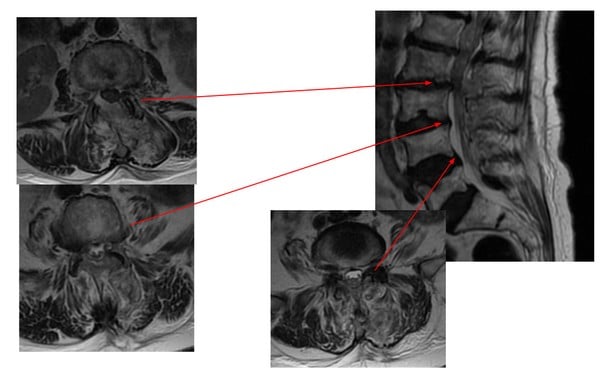

Endoskopowy zabieg w obrębie kręgosłupa lędźwiowego – odbarczenie na wielu poziomach

U pacjentki zastosowano endoskopową technikę UBE. Ponieważ szczególną zaletą metody jest możliwość jednoczesnego odbarczenia na wielu poziomach, u pacjentki wykonano odbarczenie na 3 poziomach podczas jednego zabiegu. UBE to minimalnie inwazyjna technika, która pozwala na precyzyjne usunięcie uszkodzonej tkanki przy niewielkim ryzyku powikłań i skróconym czasie rekonwalescencji, co może być szczególnie istotne u pacjentów w podeszłym wieku.

Zastosowanie metody u naszej pacjentki pozwoliło na skuteczne odbarczenie kanału kręgowego przy jednoczesnym zachowaniu maksymalnej funkcjonalności kręgosłupa.

Na zdjęciach wykonanych po zabiegu widoczne jest odbarczenie w obrębie wszystkich poziomów. Po usunięciu przerośniętych więzadeł żółtych oraz przyśrodkowych części stawów międzykręgowych w obrębie segmentów L2/L3, L3/L4 i L4/L5, nastąpiło poszerzenie kanału kręgowego.